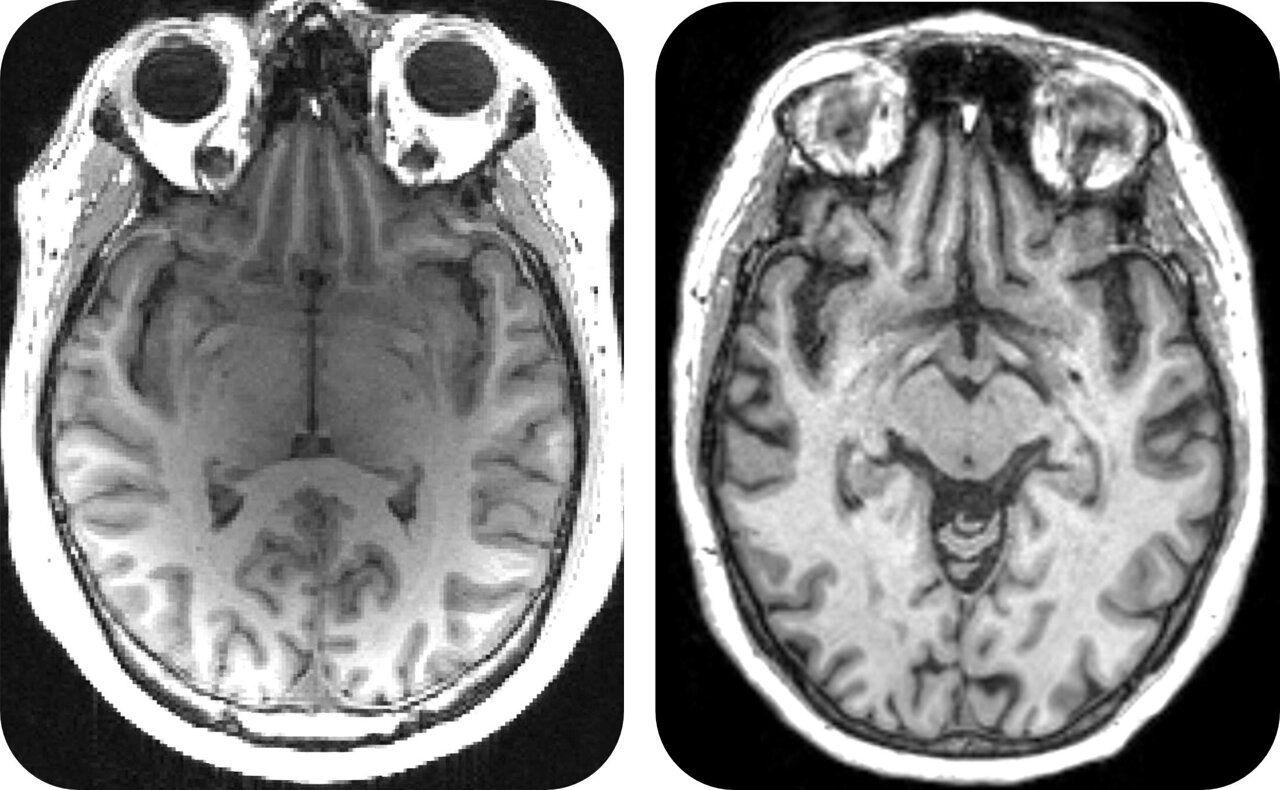

Scientists have used an AI model to reassess the results of a completed clinical trial for an Alzheimer's disease drug. They found that the drug slowed cognitive decline by 46% in a group of patients with early-stage, slow-progressing mild cognitive impairment -- a condition that can progress to Alzheimer's. Using AI allowed the team to split trial participants into two groups: either slowly or rapidly progressing towards Alzheimer's disease. They could then look at the effects of the drug on each group. The work appears in Nature Communications. More precise selection of trial participants in this way could help select patients most likely to benefit from treatment, with the potential to reduce the cost of developing new medicines by streamlining clinical trials. The AI model developed by researchers at the University of Cambridge predicts whether and how quickly people at early stages of cognitive decline will progress to full-blown Alzheimer's. It gives predictions for patients that are three times more accurate than standard clinical assessments based on memory tests, MRI scans and blood tests. Using this patient stratification model, data from a completed clinical trial -- which did not demonstrate efficacy in the total population studied -- was re-analyzed. The researchers found that the drug cleared a protein called beta amyloid in both patient groups as intended -- but only the early stage, slow-progressing patients showed changes in symptoms. Beta amyloid is one of the first disease markers to appear in the brain in Alzheimer's disease. The new findings have significant implications. Using AI to separate patients into different groups, such as slow versus rapidly progressing towards Alzheimer's disease, allows scientists to better identify those who could benefit from a treatment approach -- potentially accelerating the discovery of much-needed new Alzheimer's drugs. Professor Zoe Kourtzi in the University of Cambridge's Department of Psychology, senior author of the report, said, "Promising new drugs fail when given to people too late, when they have no chance of benefiting from them. With our AI model, we can finally identify patients precisely, and match the right patients to the right drugs. This makes trials more precise, so they can progress faster and cost less, turbocharging the search for a desperately-needed precision medicine approach for dementia treatment. "Our AI model gives us a score to show how quickly each patient will progress towards Alzheimer's disease. This allowed us to precisely split the patients in the clinical trial into two groups -- slow- and fast-progressing, so we could look at the effects of the drug on each group." Health Innovation East England, the innovation arm of the NHS in the East of England, is now supporting Kourtzi to translate this AI-enabled approach into clinical care for the benefit of future patients. Joanna Dempsey, Principal Advisor at Health Innovation East England, said, "This AI-enabled approach could have a significant impact on easing NHS pressure and costs in dementia care by enabling more personalized drug development -- identifying which patients are most likely to benefit from treatment, resulting in faster access to effective medicines and targeted support for people living with dementia." Drugs like this are not intended as cures for Alzheimer's disease. The aim is to reduce cognitive decline so that patients don't get worse. Dementia is the UK's leading cause of death, and a major cause of mortality globally. It costs $1.3 trillion per year, and the number of cases is expected to triple by 2050. There is no cure, and patients and families face great uncertainty. Despite decades of research and development, clinical trials of treatments for dementia have been largely unsuccessful. The failure rate for new treatments is unreasonably high at over 95%, despite $43 billion having been spent on research and development. Progress has been hampered by the wide variation in symptoms, disease progression and responses to treatment among patients. Although new dementia drugs have recently been approved for use in the US, their risk of side effects and insufficient cost-effectiveness have prevented health care adoption in the NHS. Understanding and accounting for the natural differences among individuals with a disease is crucial, so that treatments can be tailored to be most effective for each patient. Alzheimer's disease is complex, and although some drugs are available to treat it, they don't work for everybody. "AI can guide us to the patients who will benefit from dementia medicines, by treating them at the stage when the drugs will make a difference, so we can finally start fighting back against these cruel diseases. Making clinical trials faster, cheaper and better, guided by AI, has strong potential to accelerate the discovery of new precise treatments for individual patients, reducing side effects and costs for health care services," said Kourtzi. She added, "Like many people, I have watched hopelessly as dementia stole a loved one from me. We've got to accelerate the development of dementia medicines. Over £40 billion has already been spent over thirty years of research and development -- we can't wait another thirty years."

.The AI model's predictions are reportedly three times more accurate than standard clinical assessments based on memory tests, MRI scans, and blood tests